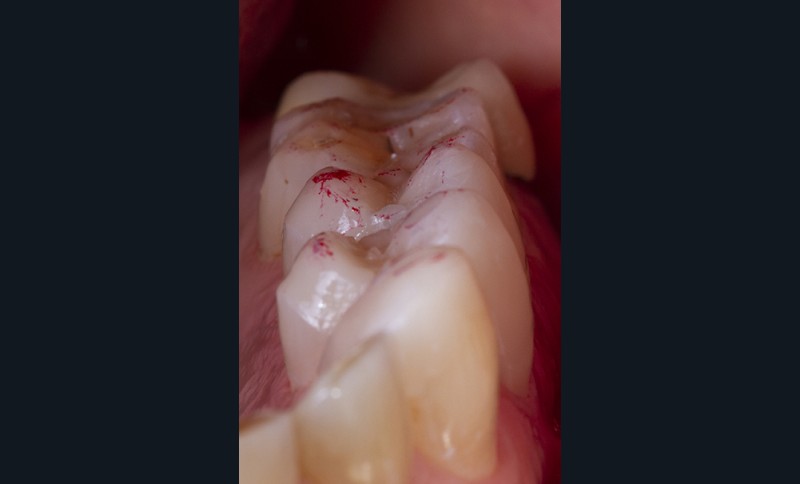

Un déplaquage est nécessaire avant d’initier les étapes de collage.

Un sablage à l’oxyde d’alumine est recommandé lorsque les usures sont marquées afin de préparer la surface de collage. Après rinçage, un mordançage à l’acide orthophosphorique est réalisé pendant 30 secondes sur l’émail et 15 secondes sur la dentine. Après un rinçage scrupuleux, un adhésif est étalé sur l’ensemble des surfaces mordancées, soufflé puis photopolymérisé (fig. 5).